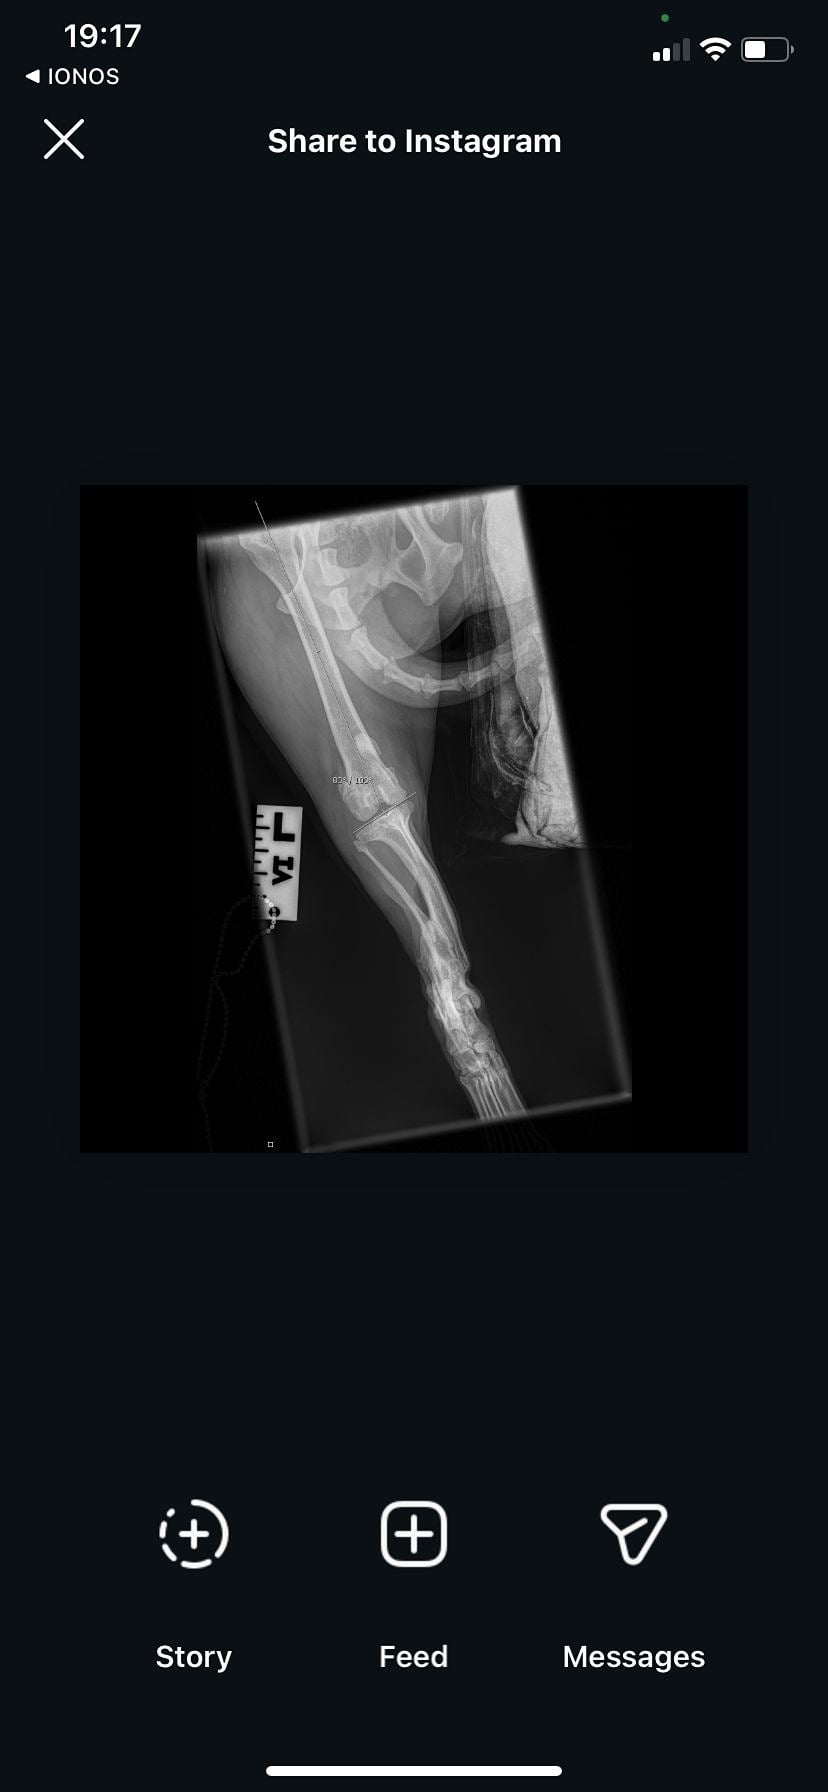

Upon arriving at Oakwood, we noticed Billi was not fully weight bearing on his BL leg. We put him on pain meds and kennels rest but when this wasn't working, we sent him straight from X-rays.

Unfortunately, Billi has several problems with his legs that are going to require surgical intervention.

His back right leg: He has luxating patella grade 2

His left leg: He has luxating patella grade 3/4. He also has an old break that has healed completely abnormally in this leg, you can feel the bone almost protruding through his skin, even with the gentlest touch.

To make the surgery even more difficult, the break has healed so abnormally that it has left Billi with a leg 2 inches shorter than his other. His hips are also at a 20% rotational angle which doesn't effect Billie is every day life, but will effect the difficulty of the surgery and so we are currently in discussions with specialists as to what the best plan of action is going to be.